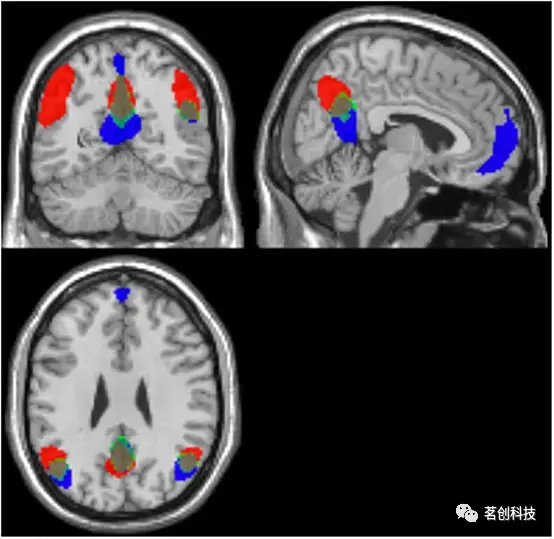

使用与每个参与者模板DMN(1I-间歇静息条件和1C-连续静息条件)相关性最高的成分进行的连接分析显示出大量的空间重叠。这表明DMN在间歇和连续静息条件下都被激活,参见图4。此外,在所有47名参与者中,本研究计算了与模板DMN图具有最高和次高相关性的成分的概率图(1I和2I代表间歇静息条件和1C和2C代表连续静息条件)。概率图显示,各成分之间的重叠在DMN的额部ROI较弱,而在后部ROI区域的重叠最强,见图5。

关联分析和概率图

使用与模板DMN图相关性最高的均值参与者的成分来选择单个参与者的成分,以便在每个个体的所有相对成分图像中进行二级关联分析(单因素方差分析,随机效应)。这允许量化在两种静息态下已识别的DMN成分之间的相似性水平。采用SPM12进行关联分析(conjunction analysis)。所有相关的成分图(每个参与者和条件各一个)被纳入二阶分析(单因素方差分析)。在对模型进行估计后,定义多重对比进行比较。对统计图进行多重比较(FWE)校正,并选择p值为0.05的显著性阈值且聚类程度为10体素进行所有比较。此外,为了测试与模板DMN图相关性最高和次高的成分的空间重叠,本研究使用SPM12计算了所有成分和所有参与者的概率图。首先,使用z>1.96(相当于p<0.05)的阈值对所有成分进行二值化。其次,将所有二值化的成分按体素相加,乘以100并除以图像总数量。因此,显示的体素值表示在两种条件下所有参与者中存在最高和次高的DMN相关成分的概率(%)。